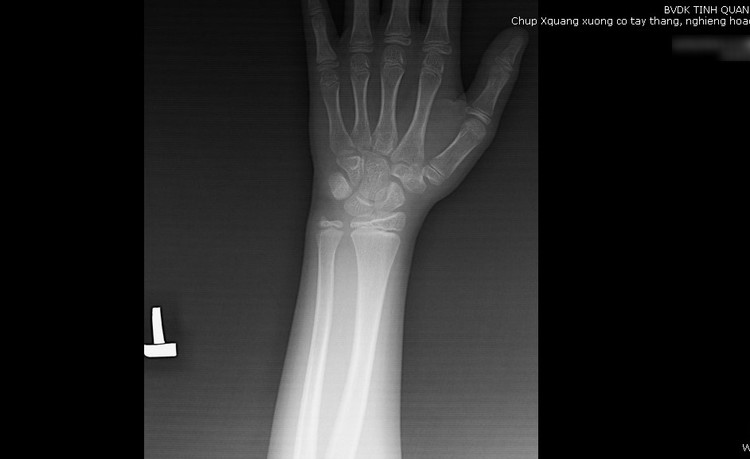

| X-quang xương cổ tay trái của trẻ 7 tuổi dậy thì sớm - Ảnh BVCC |

Bác sĩ Lan cho hay, để chẩn đoán xác định, trẻ đến khám sẽ được chỉ định chụp Xquang cổ tay trái để xác định tuổi xương, làm các xét nghiệm máu để kiểm tra nồng độ hormone, siêu âm tử cung phần phụ, siêu âm tinh hoàn-tuyến thượng thận, tùy theo kết quả sẽ có thể chụp MRI sọ não để chẩn đoán nguyên nhân.